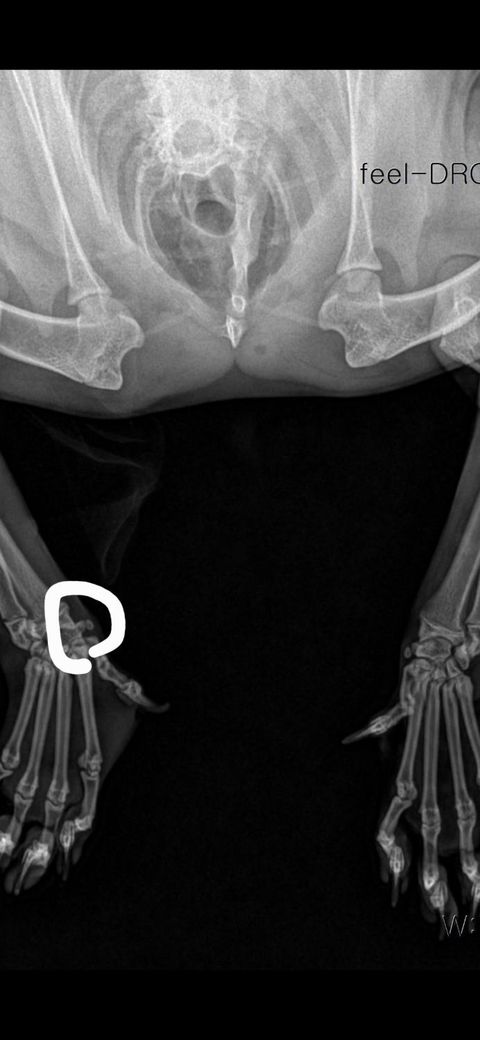

탈구 된 직후 엑스레이 사진

탈구 된 직후 찍은 발

3일차 현재 발